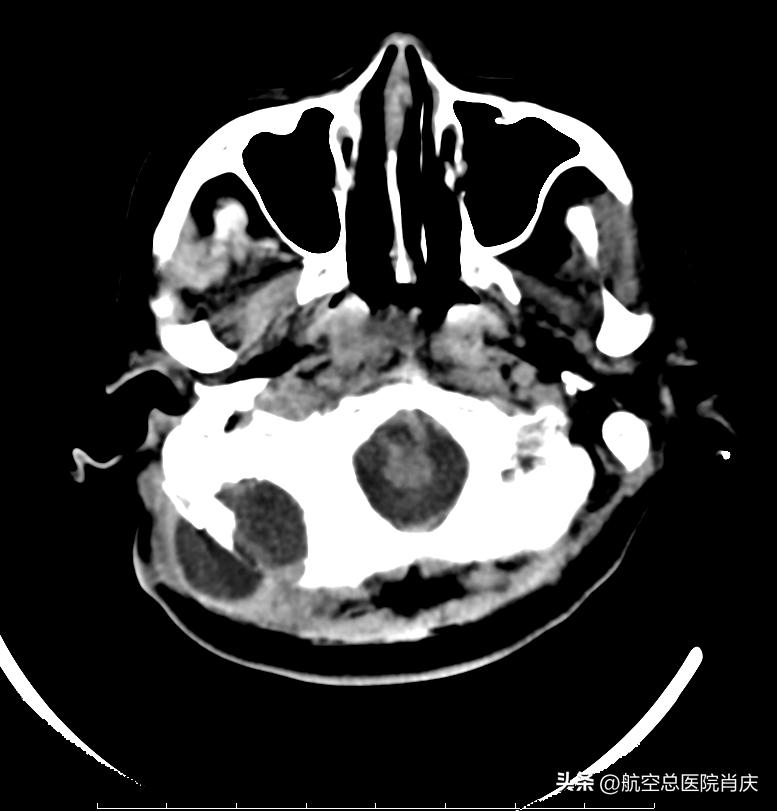

术前

经过多次会诊和科学诊断评估之后,肖庆主任团队为黄女士在全麻下顺利完成了脑脊液切口漏修补术+阔筋膜切取术+皮瓣整形修复术。脑脊液漏修补有很多材料 ,首选自体材料,自身组织的相容性还是要高于各类人工材料。术后第三天拔除皮下引流,复查头颅CT,患者病情恢复良好,未见脑脊液漏,已经可以回原医院继续进行康复治疗。